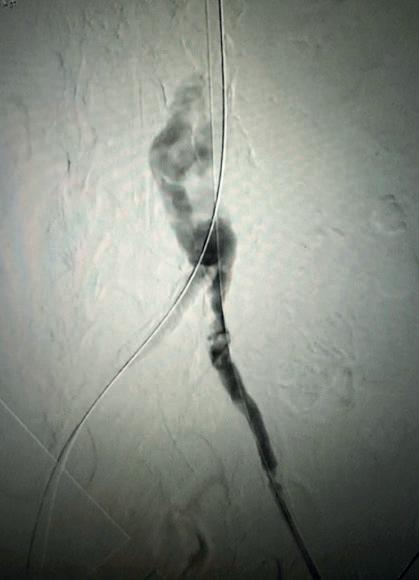

For those that qualify for intervention based on currently used criteria, vascular access is obtained in the standard fashion with ultrasound guidance. Caval venography is performed to ensure no anatomic abnormality, thrombosis or clot in transit. The right heart is then catheterised—I am a fan of the angled pigtail more so than a balloon-tipped catheter such as the Swan-Ganz as I feel its shape mirrors the anticipated trajectory. For each one of my PE interventions, a full right heart catheterisation is performed. A comfort with waveform analysis traversing right atrium, right ventricle and into the main pulmonary artery is paramount. These are standard displays in a cardiac catheterisation laboratory although not usual in the operating suite, so depending on your site of care, it is